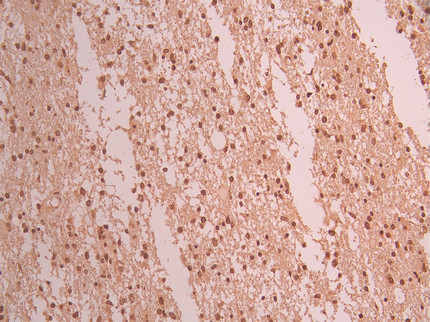

IHC image of CSB-RA552120A0HU diluted at 1:100 and staining in paraffin-embedded human spleen tissue performed on a Leica BondTM system. After dewaxing and hydration, antigen retrieval was mediated by high pressure in a citrate buffer (pH 6.0). Section was blocked with 10% normal goat serum 30min at RT. Then primary antibody (1% BSA) was incubated at 4°C overnight. The primary is detected by a Goat anti-rabbit polymer IgG labeled by HRP and visualized using 0.05% DAB.